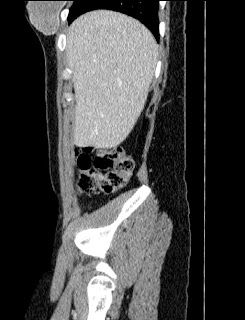

44 year old female with a long medical history. Undergone repeated surgeries for prox. 30 years. Not always fully understood what the purpose has been or expected outcome from all the procedures.

2010